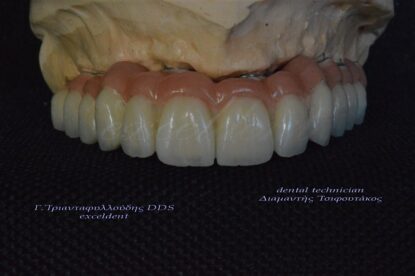

Ολική αποκατάσταση στόματος με ακίνητες γέφυρες στηριζόμενες σε εμφυτεύματα

Ακόμη ένα περιστατικό ολικής στοματικής αποκατάστασης ασθενούς με ακίνητες γέφυρες στηριζόμενες σε εμφυτεύματα(8 στην άνω και 7 στην κάτω γνάθο).